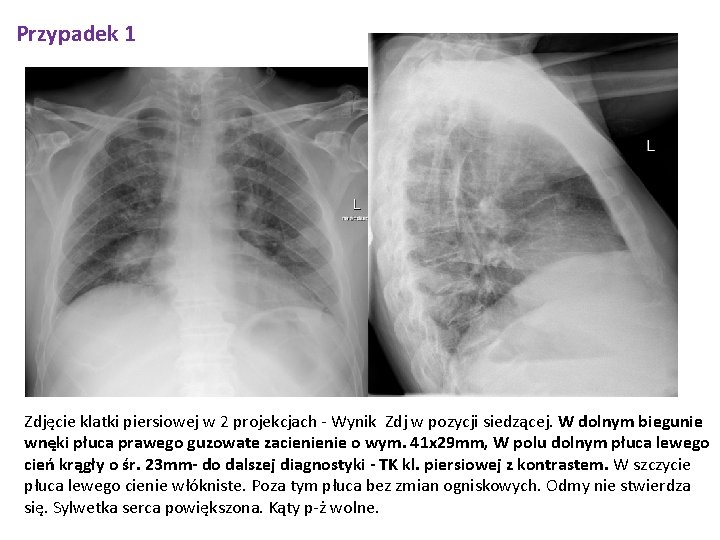

Przypadek 1 Zdjęcie klatki piersiowej w 2 projekcjach - Wynik Zdj w pozycji siedzącej. W dolnym biegunie wnęki płuca prawego guzowate zacienienie o wym. 41 x 29 mm, W polu dolnym płuca lewego cień krągły o śr. 23 mm- do dalszej diagnostyki - TK kl. piersiowej z kontrastem. W szczycie płuca lewego cienie włókniste. Poza tym płuca bez zmian ogniskowych. Odmy nie stwierdza się. Sylwetka serca powiększona. Kąty p-ż wolne.